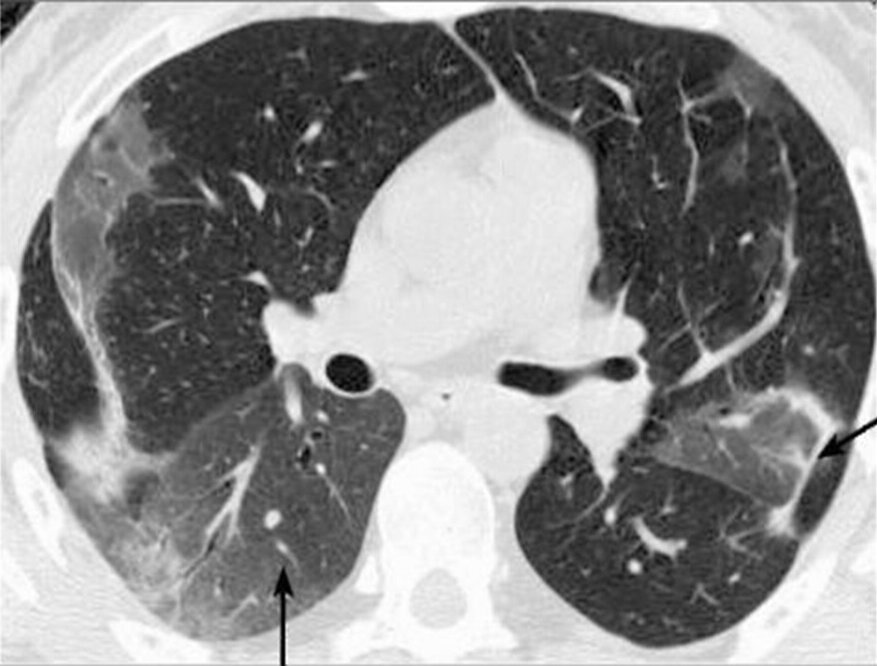

Клиническая практика показывает, что наиболее частым и характерным признаком патологических изменений в легочной ткани при COVID-19 на снимках КТ является наличие симптома «матового стекла». При прогрессировании процесса зоны «матового стекла» трансформируются в участки консолидации (уплотнение легочной ткани), которые при неблагоприятном течении заболевания вовлекают большие объемы легочной ткани.

Зоны "матового стекла" можно отчетливо увидеть на снимке КТ